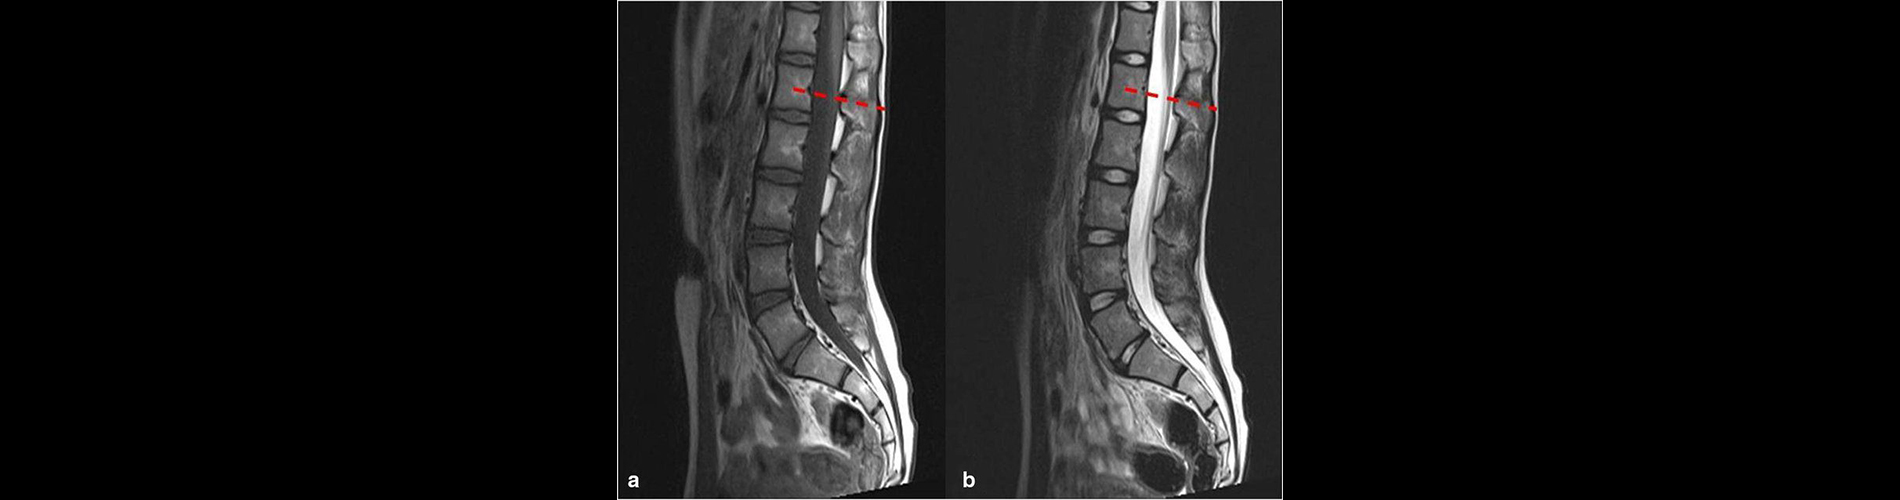

Lomber MR , bel bölgesindeki (lomber omurga) omurlar, omurilik, sinir kökleri, diskler ve çevre yumuşak dokuları detaylı bir şekilde görüntülemek için kullanılan bir yöntemdir. Radyasyon içermemesi ve yumuşak dokuları çok net görüntüleyebilmesi nedeniyle bel hastalıklarının teşhisinde sıkça tercih edilir.

• Odak Alanı: Bel bölgesindeki omurlar (L1-L5), sakral omur, omurilik, sinir kökleri, intervertebral diskler, bağlar ve yumuşak dokular.

1. Detaylı Görüntüleme: o Omurga, diskler, sinir kökleri ve çevre dokular yüksek çözünürlükte görüntülenir.

3. Doğru Tanı: o Bel fıtığı, sinir kökü basısı veya spinal stenoz gibi sorunların doğru teşhisinde etkilidir.